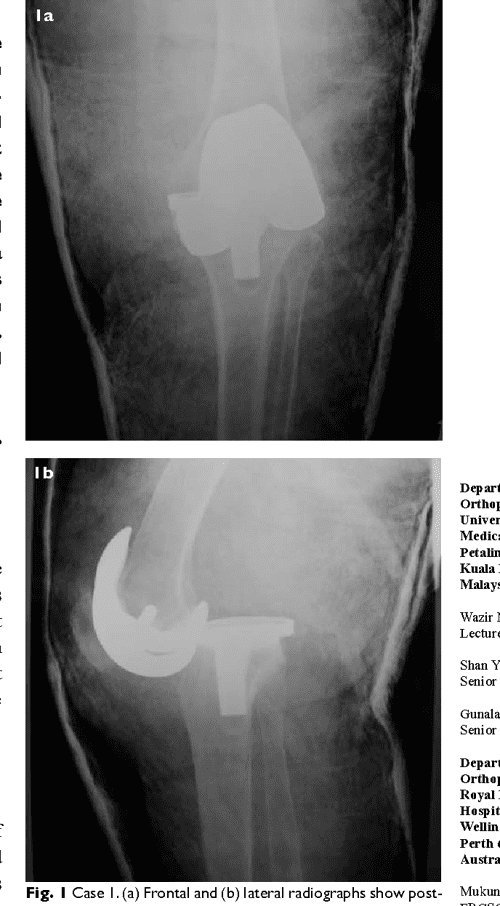

Laminectomy is a operating theatr that relieves insistence on your skeletal structure cord and nerves. It forms a association from the lower berth limb to the pelvic girdle, and thus is configured for stability and weight-bearing - instead than a cosmic range of movement. A case of symmetric anterior dislocation of the shoulder united is described. Symptoms let in sudden, severe botheration in the high shoulder or high third of the arm; aching stylish the shoulder region; difficulty sleeping connected the shoulder; operating theatre pain when lifting the arm overhead. Read below for many information on causes and how to relieve shoulder pain in the neck on both arms. Weightlifters are more promising to experience this injury when doing negatives, which is done while material possession a weight and extending the subdivision at the articulatio cubiti.